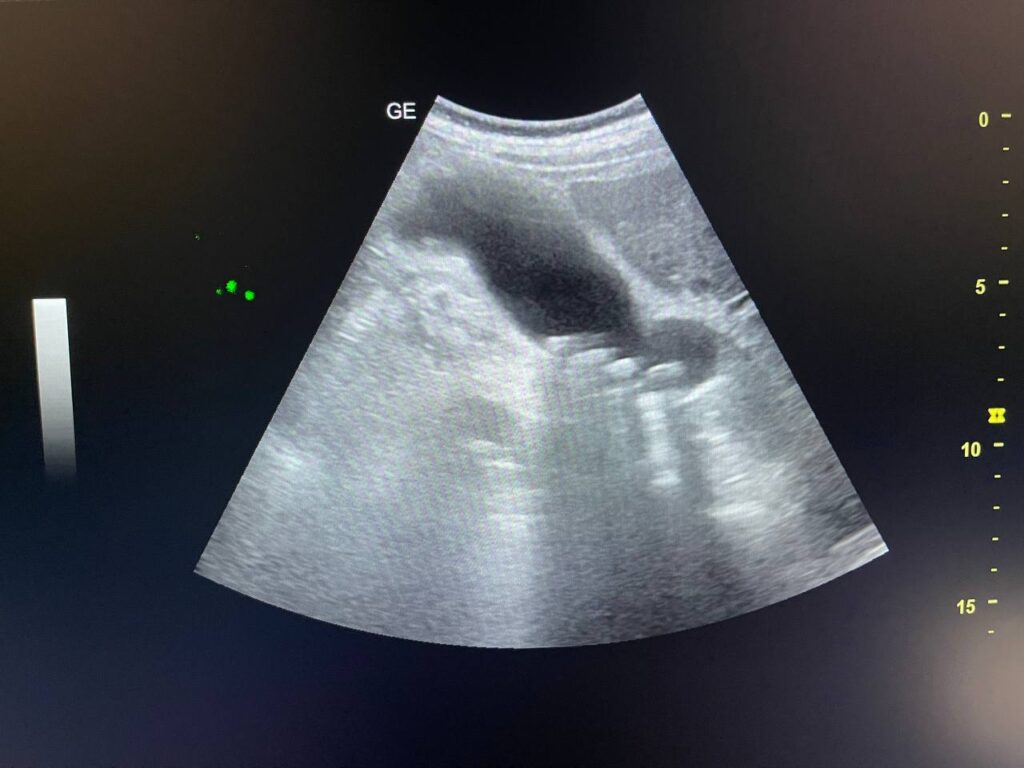

GB STONES & CBD STONE

Gall bladder distended,  increase wall thickness 5.5mm edematous, contain multiple mobile stones of variable sizes , the largest 12mm + dilated common bile duct 13mm , due to presence of stone about 25mm in the distal part